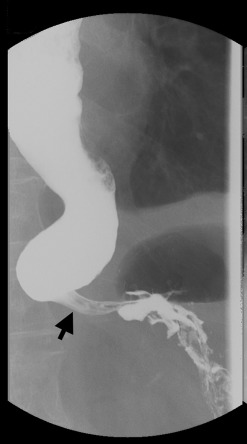

Physical examination demonstrated a thin woman. Her height was 158 cm and weight 48 kg. Her abdomen was soft without rebound tenderness. The laboratory tests were normal, apart from hypokalemia (K 3.4 mmol/L, normal range 3.5–5.3 mmol/L) and normocytic anemia (Hb 11.9 g/dL, normal range 12–14 g/dL). An esophagogram demonstrated a markedly dilated esophagus with a “bird-beak” appearance at the GE junction (Fig. 2 ). Idiopathic achalasia was preliminarily diagnosed based on the above findings, although the patients age and short duration of symptoms were not consistent with the diagnosis. Repeated EGD demonstrated a very tight GE junction (Fig. 3 A) with retention of some food residues and pills in the lower third of the esophagus (Fig. 3 B). Besides, the endoscope could not pass the GE junction into the stomach. However, esophageal manometry demonstrated a normal pattern of esophageal peristalsis. Based on the endoscopic findings and manometric features, pseudoachalasia was suspected. Abdominal computed tomography demonstrated a hypovascular tumor in the left lobe of the liver (Fig. 4 A, arrows). Moreover, the tumor encased the lower end of the esophagus (Fig. 4 B, arrows). Thus, the diagnosis of pseudoachalasia caused by liver tumor was made. At laparotomy, the liver tumor was deemed unresectable and biopsy specimens were taken. A pathological examination of the biopsy specimens showed cuboidal tumor cells with pleomorphic and hyperchromatic nuclei arranged in a ductular or glandular pattern within the desmoplastic stroma, the findings being consistent with cholangiocarcinoma (Fig. 5 ). Finally, the patient died due to disease progression 1 year later.

Esophagogram demonstrating a markedly dilated esophagus with a “bird beak” ...

Figure 2.

Esophagogram demonstrating a markedly dilated esophagus with a “bird beak” tapering at the gastroesophageal junction (arrow).

It is often difficult to distinguish between pseudoachalasia and idopathic achalasia based on the clinical features, radiologic images, and endoscopic findings. Certain historical features can help raise the suspicion of the presence of a malignant tumor. A short duration of symptoms (<1 year), presentation later in life (at the age of 50–60 years), and unexplained weight loss (6.8–9.0 kg) are all more typical of malignancy than of idiopathic achalasia [8]  ;  [9] . Although a few studies have reported that these criteria are poor predictors of malignancy and are not especially helpful in individual cases, the clinical features of our patient were all compatible with the abovementioned criteria. Moreover, esophageal manometric findings of a hypertensive (48 mmHg), nonrelaxing LES and a total lack of esophageal peristalsis may be indicative of achalasia. In our present case, an esophagogram demonstrated a markedly dilated esophagus with a typical bird-beak appearance, leading to the initial diagnosis of idiopathic achalasia. However, repeated EGD showed stenosis of the GE junction, and esophageal manometry revealed a normal pattern of esophageal peristalsis, not suggestive of idiopathic achalasia. A reasonable explanation for the presentation of pseudoachalasia in our patient is that the tumor cells encircled the distal esophagus, producing a constricting segment, but did not infiltrate the esophageal myenteric plexus or directly affect the vagus nerves.